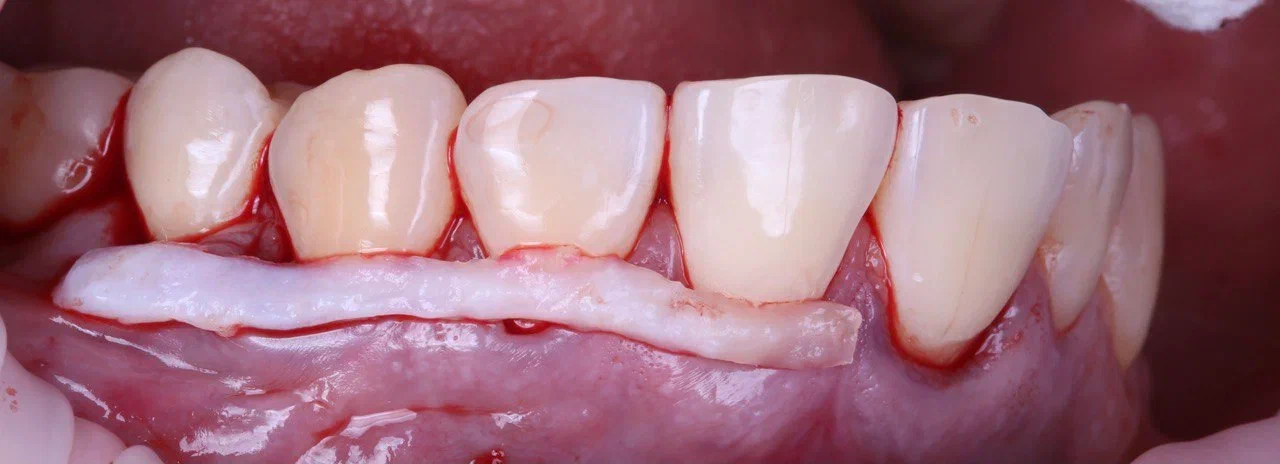

- с области твёрдого нёба пациента забирается участок слизистой нужного размера (трансплантат), который подсаживается и подшивается внутрь кармана;

Белый червячок на десне — тот самый трансплантат